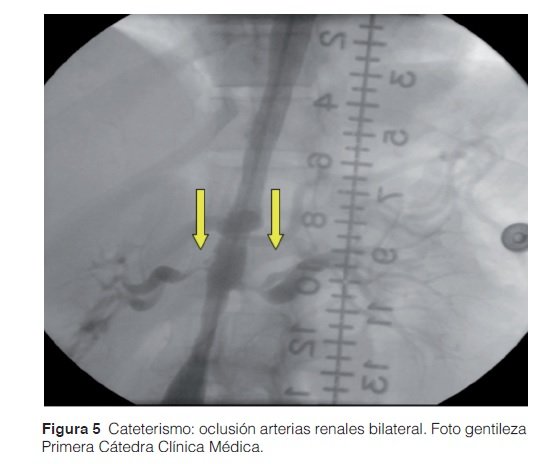

Se realizó cateterismo cardíaco donde se constató una estenosis del 60% en la aorta a nivel infrarrenal (Figura 4). A nivel del nacimiento de las arterias renales (Figura 5) se observó en el lado derecho una oclusión proximal del 95 % y en el lado izquierdo una oclusión del 95 % con buen lecho distal. Por esta razón se procedió a la colocación de tres stents autoexpansibles en dichos niveles. Con posterior normalización de cifras tensionales y mejoría clínica.